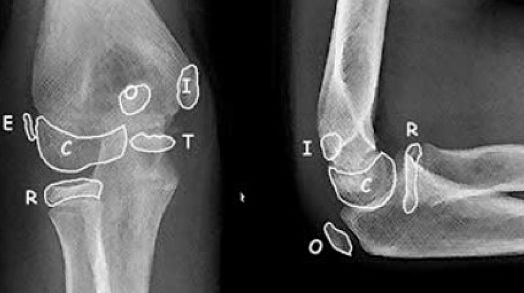

La aparición de centros de osificación secundarios en el codo, siguen un orden determinado. La regla nemotécnica CRITOE permite recordar el orden de aparición de dichos centros (Figura 1).

Figura 1: Aparición de los centros de osificación. 1 año- C: capitelum, 3 años-R: cabeza Radial, 5 años- I: epicóndilo Interno, 7 años- T: Tróclea, 9 años- O: Olecranon y 11 años- E: Epicóndilo lateral.